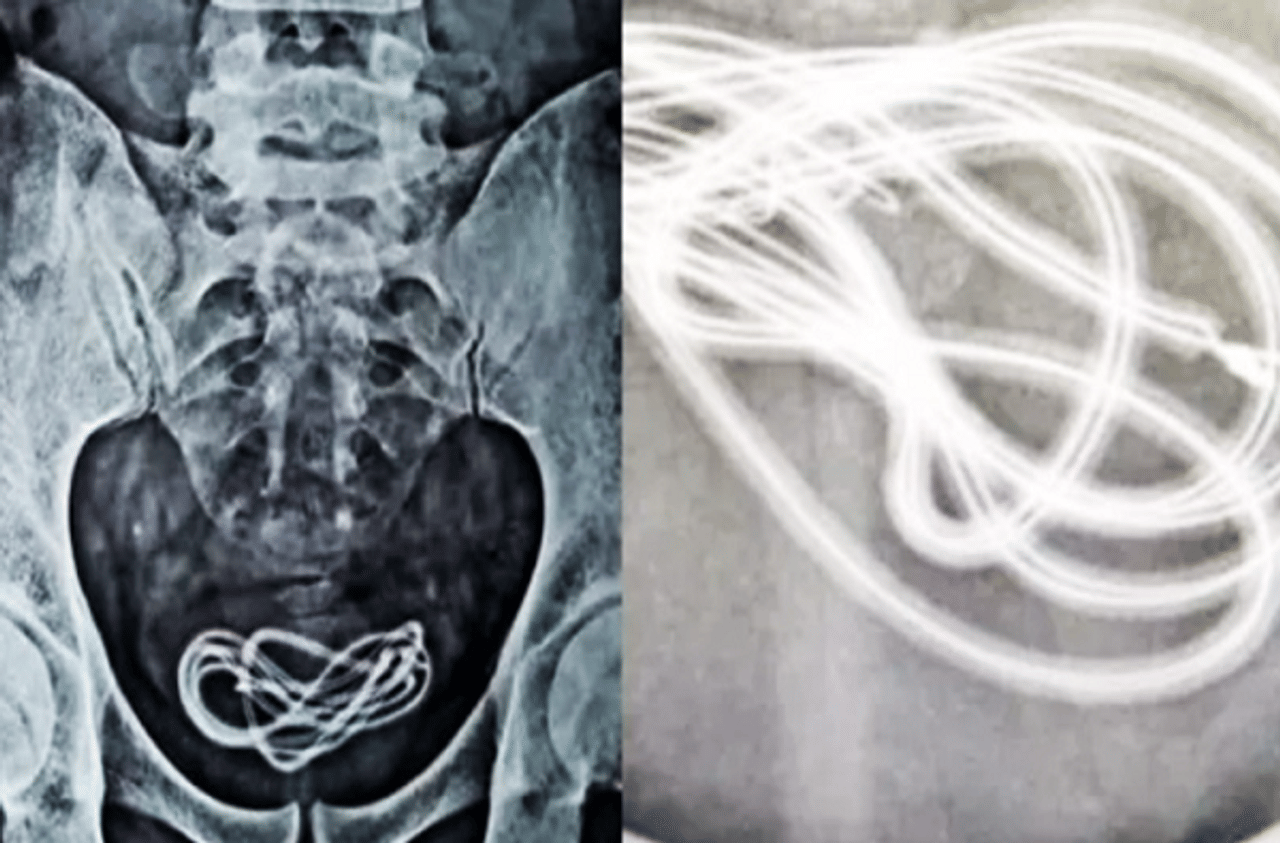

गेले काही दिवस तरुणाच्या पोटात दुखत होते. त्यामुळे कुटुबियांनी त्याला डॉक्टरकडे नेले. डॉक्टरांनी त्याचे पोट स्कॅन केले पण काही दिसले नाही. त्यानंतर डॉक्टरांनी एक्सरे काढले. एक्सरे काढल्यानंतर सजमले की, तरुणाच्या मुत्राशयात मोबाईल चार्जरची वायर आहे. हे पाहून डॉक्टरांनाही धक्का बसला. दरम्यान, डॉक्टरांनाही प्रश्न पडला की, ही वायर तरुणाच्या पोटात गेली कशी.

“गेले 25 वर्ष मी शस्त्रक्रिया करत आहे. पण अशा प्रकारची घटना पहिल्यांदाच दिसली. रुग्णाच्या पोटातून मोबाईल चार्जरची वायर काढली आहे. या घटनेचे फोटो आणि व्हिडीओही तुम्ही पाहू शकता. रुग्णावर यशस्वीरित्या शस्त्रक्रिया केली आहे. पण रुग्णाची मानसिक स्थिती व्यवस्थित नाही”, असं डॉक्टर वलियुल इस्लाम यांनी सांगितले.